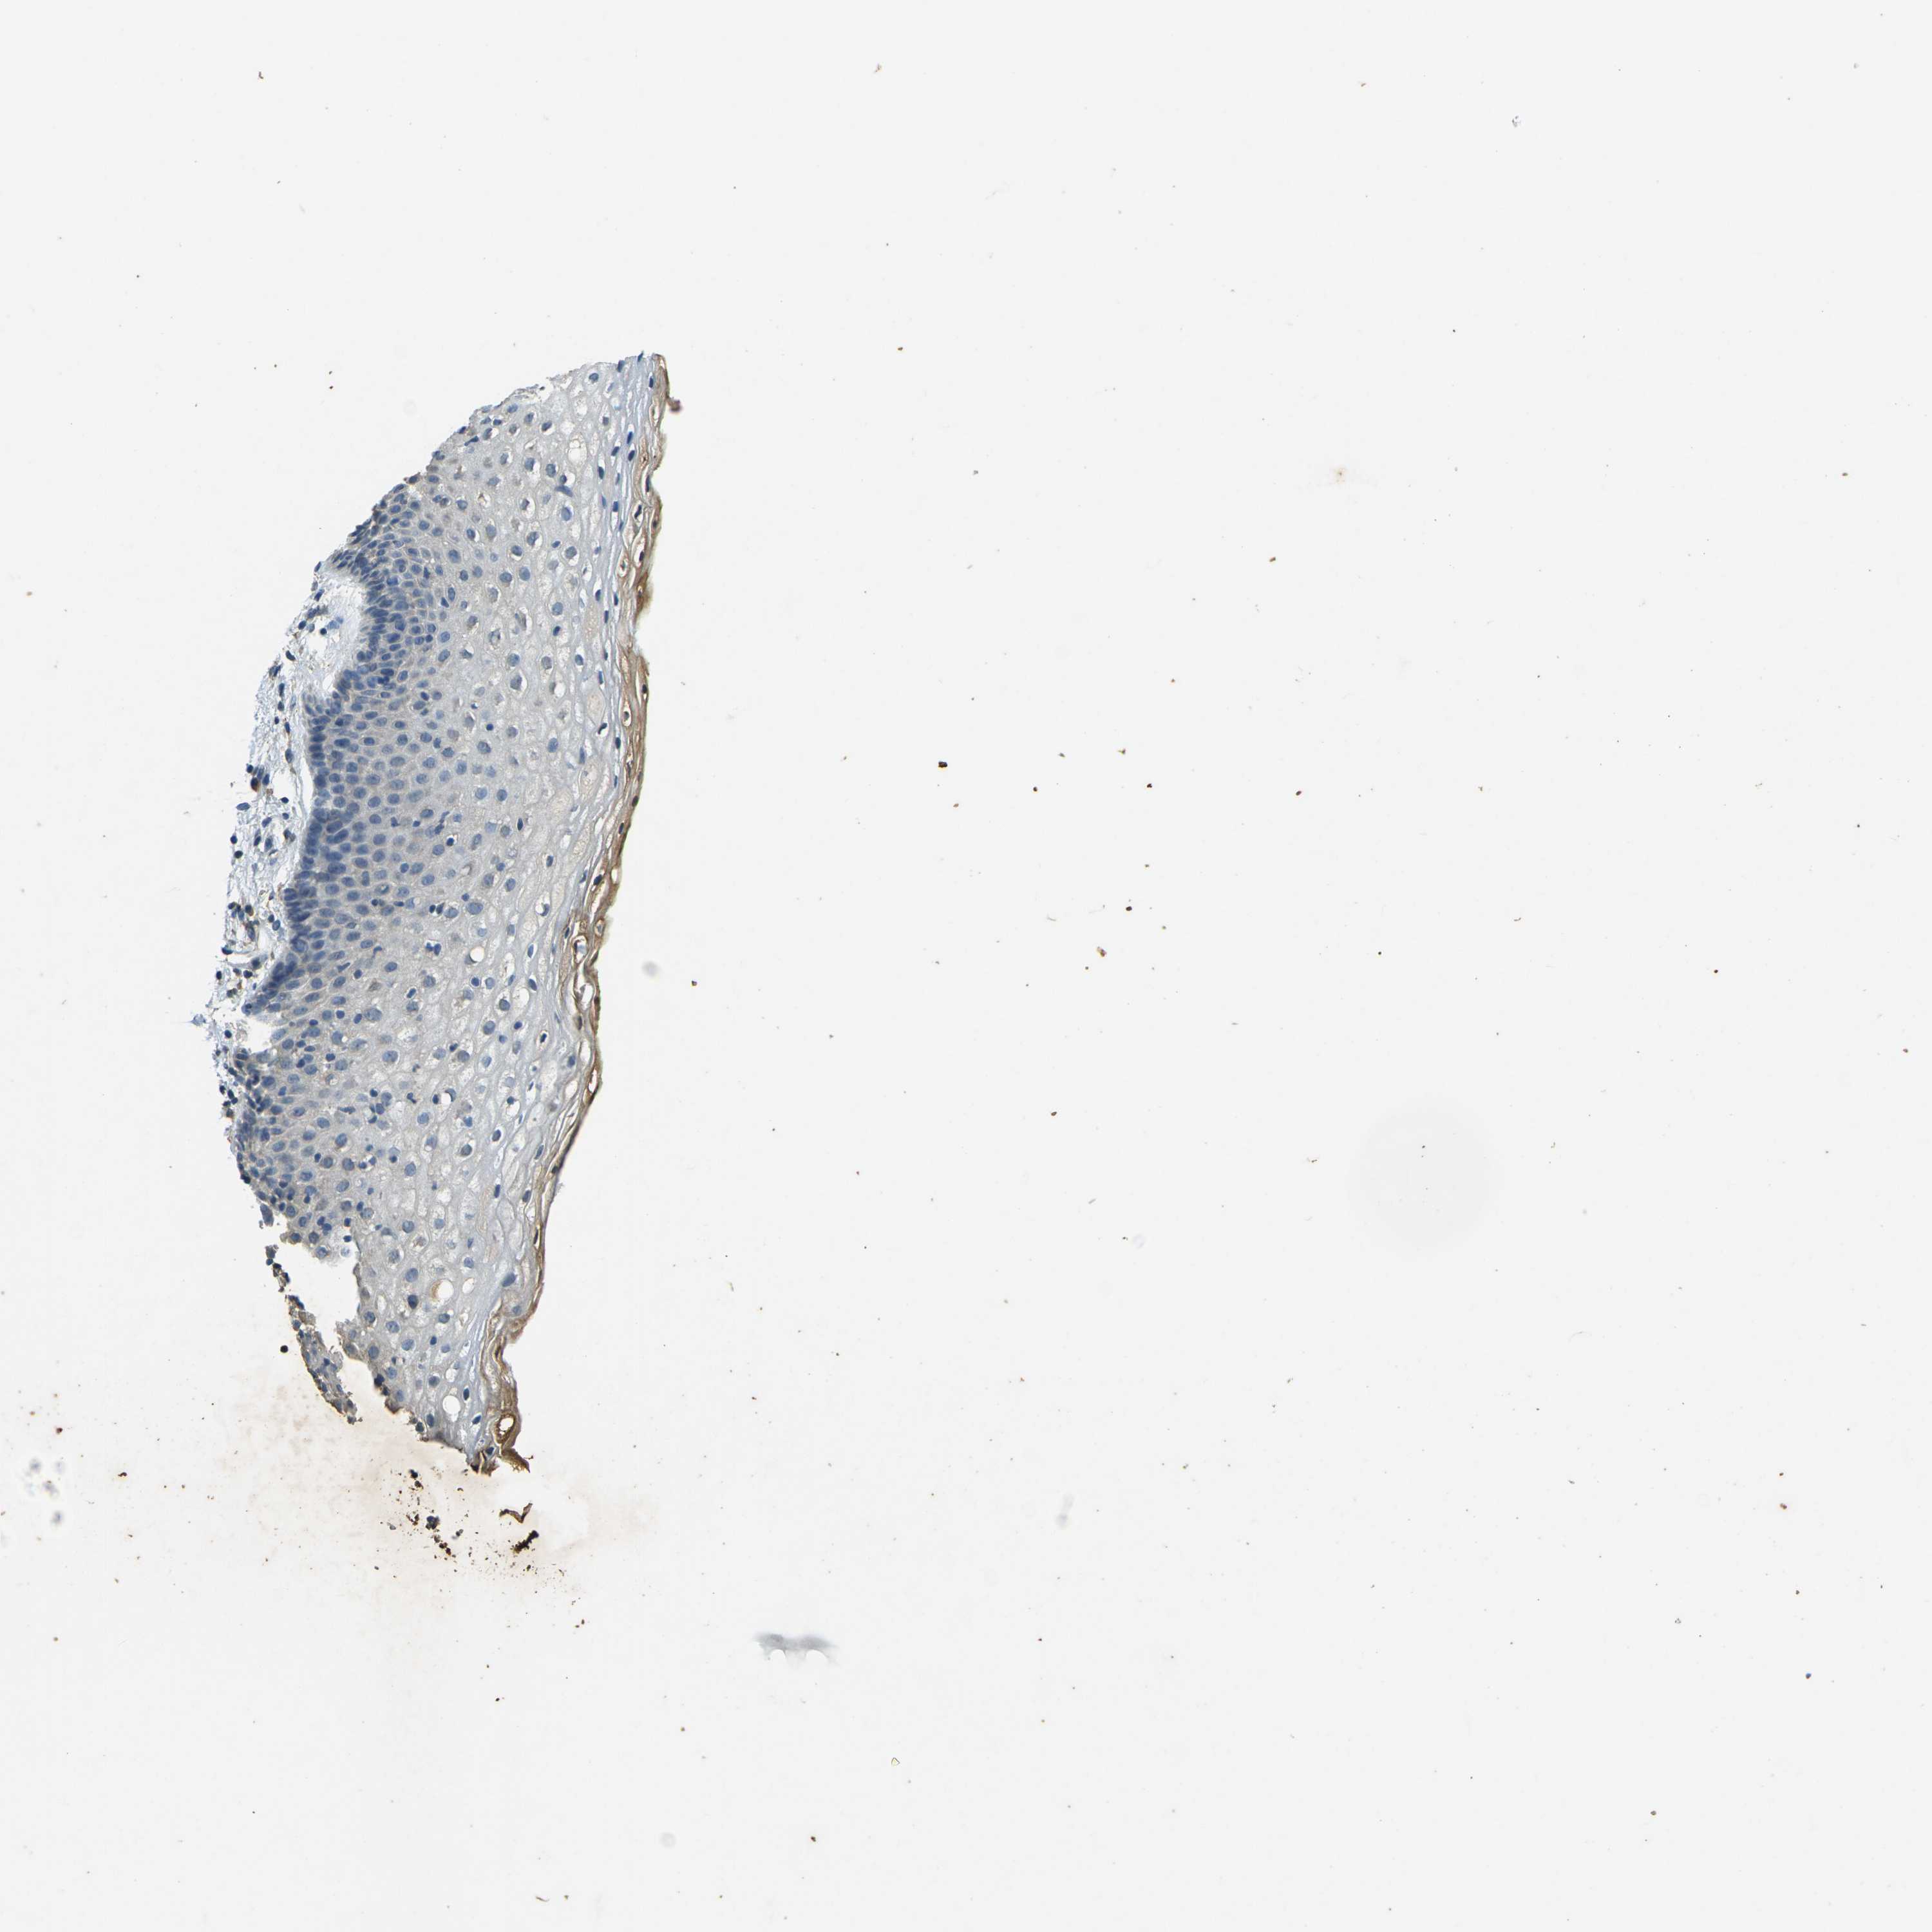

VAGINA - Antibody stainingi

Antibody staining in the annotated cell types in the current human tissue is reported as not detected, low, medium, or high, based on conventional immunohistochemistry profiling in selected tissues. This score is based on the combination of the staining intensity and fraction of stained cells.

Each image is clickable and will lead to virtual microscopy that enables deeper exploration of all samples and also displays staining intensity scores, fraction scores and subcellular localization as well as patient and tissue information for each sample.

Antibody HPA043234Antibody CAB009526

Squamous epithelial cells Not detectedNot detected